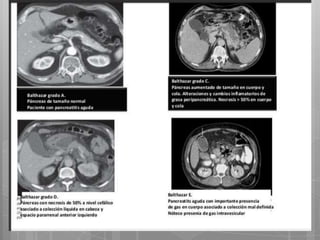

Índice tomográfico de Severidad: Balthazar

Y se considera que

si éste es ≥ 7 la

pancreatitis es

severa